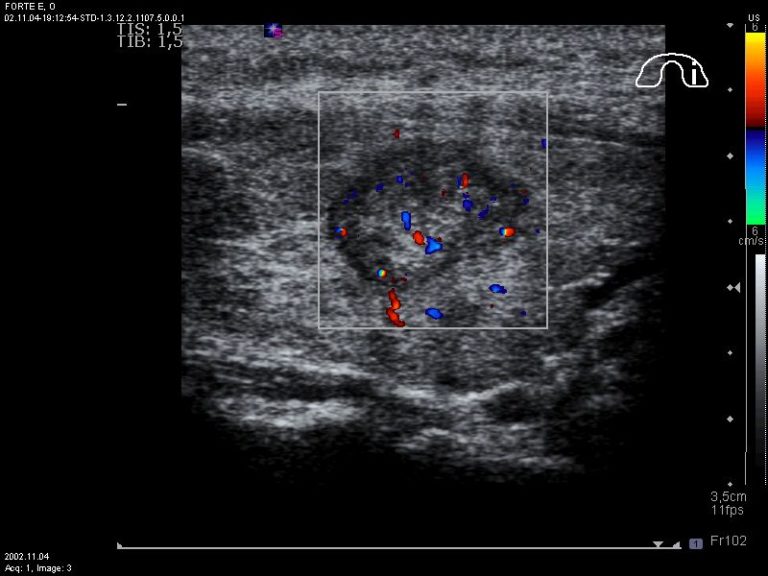

L'ecografia del collo è uno strumento imprescindibile nella diagnosi di CDT. Un'ecografia diagnostica dovrebbe essere eseguita in tutti i pazienti con il sospetto di nodulo tiroideo o gozzo nodulare, o alterazioni radiografiche riscontrante incidentalmente mediante tomografia computerizzata (TC), risonanza magnetica nucleare (RMN), o captazione alla FDG-PET (Tomografia a emissione di positroni con fluorodesossiglucosio). La visualizzazione ecografica permette di collegare con certezza l'evidenza palpatoria di una tumefazione del collo alla presenza di un nodulo della ghiandola, confermando il coinvolgimento linfonodale (se presente), identificando le caratteristiche del contenuto del nodulo (liquido, solido o misto), e localizzando correttamente la lesione. Diverse caratteristiche ecografiche quali l'ipoecogenicità del nodulo rispetto al parenchima circostante, la vascolarizzazione intranodulare, i margini irregolari, la presenza di microcalcificazioni, l'assenza di alone periferico e la forma più alta che larga nella scansione trasversale sono stati associati a una più elevata probabilità di malignità.

Con l'eccezione della presenza di linfoadenopatie cervicali sospette, che costituisce una caratteristica altamente specifica ma poco sensibile, le altre caratteristiche ecografiche di sospetto, isolatamente o in combinazione, non costituiscono parametri adeguatamente sensibili e specifici per identificare con certezza tutti i noduli maligni, anche se alcune caratteristiche o associazioni hanno un elevato potere predittivo di malignità. Inoltre, ecograficamente è possibile identificare alcuni elementi che possono distinguere la variante papillifera da quella follicolare: la prima, difatti, si presenta più spesso ipoecogena e solida, spesso con margini irregolari e aumento della vascolarizzazione. La presenza di microcalcificazioni è altamente specifica per PTC, ma queste possono essere difficili da distinguere rispetto alle lacune di colloide. Al contrario, il carcinoma follicolare è più spesso iso-iper ecogeno, con un alone spesso e irregolare, senza microcalcificazioni, e, quando inferiore ai 2 cm, non è mai associato a metastasi. Come ulteriore elemento di valutazione, oltre al color-doppler per identificare i pattern di vascolarizzazione del nodulo, recenti studi hanno dimostrato l'utilità dell'ultra-elasto-sonografia nella diagnosi differenziale dei noduli della tiroide: una tecnica promettente, che richiede ulteriore validazione con studi prospettici.

Esistono delle caratteristiche ecografiche in grado di discriminare tra linfonodi patologici e no: la forma rotondeggiante e non più ovalare, l'aspetto cistico, la vascolarizzazione interna anziché periferica, la perdita dell'ilo, l'ipoecogenicità e le microcalcificazioni. Nessuno di questi parametri, da solo, è abbastanza sensibile da potere essere condizione certa diagnostica di metastasi da carcinoma tiroideo. L'aspetto ecografico con maggiore sensibilità (100%) è la perdita dell'ilo, che però mostra una specificità del 29%. Le stazioni linfonodali coinvolte possono aiutare a porre il sospetto, risultando i livelli III-IV-VI maggiormente interessati dalla malattia rispetto al II livello. Una conferma della malignità è possibile ottenerla attraverso esame FNAc con dosaggio della tireoglobulina nel liquido di lavaggio. Quest'ultimo è affidabile anche in pazienti con anticorpi anti-Tg circolanti.